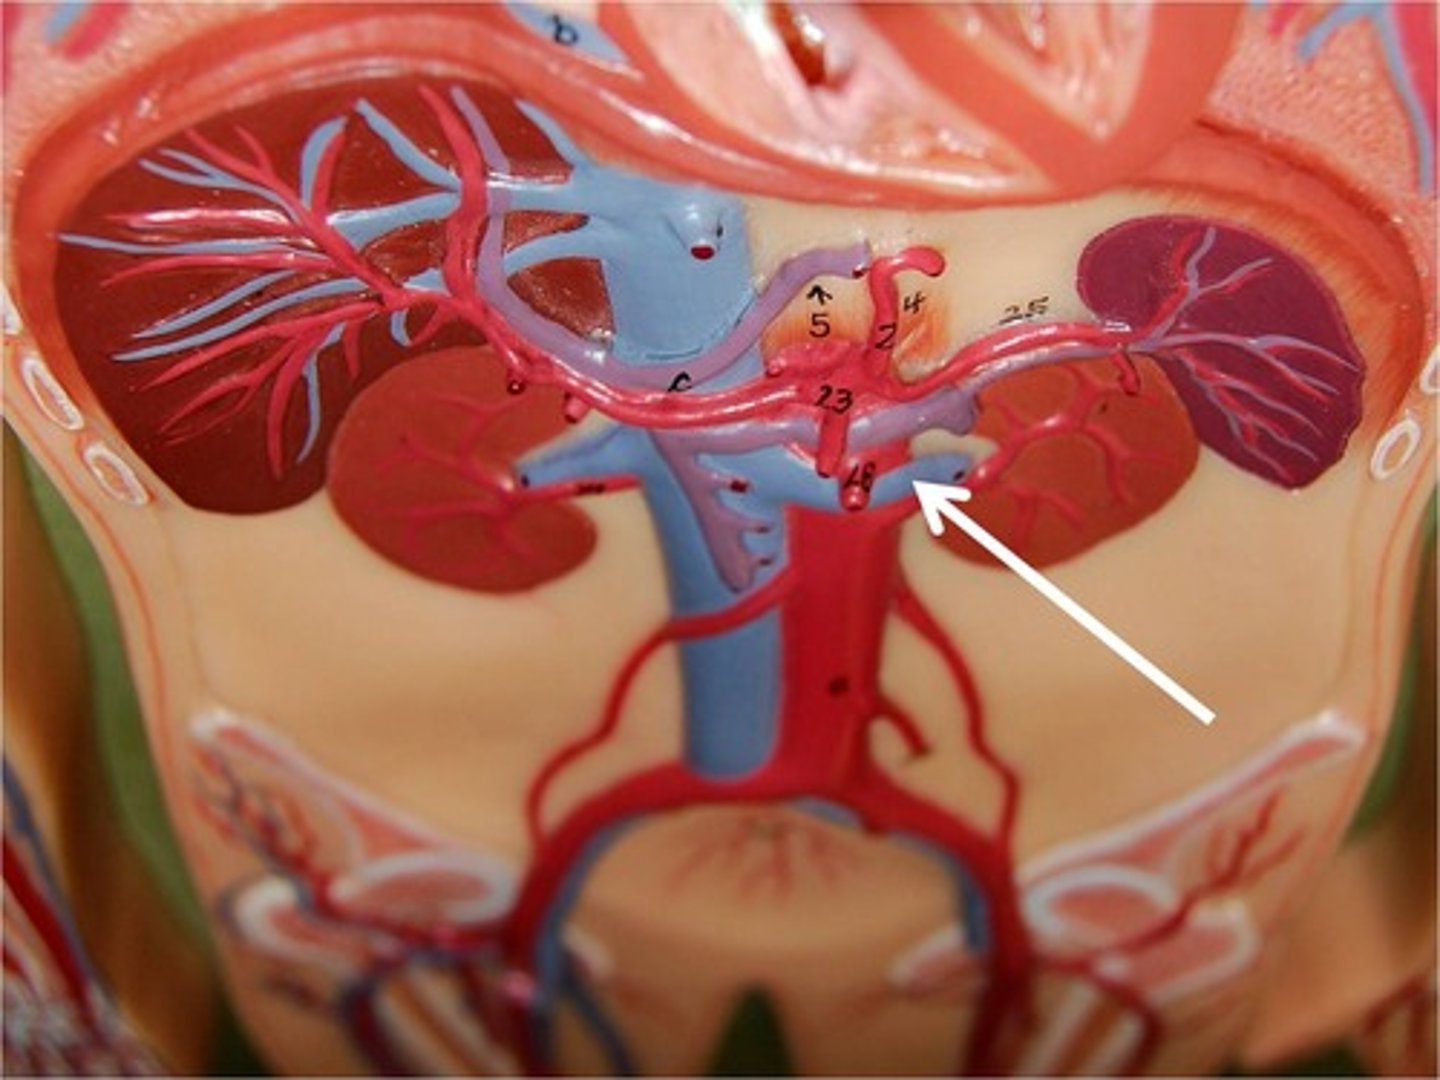

abdominal aorta

superior mesenteric artery

serves the small intestine and ascending and transverse colon

inferior mesenteric artery

serves the transverse and descending colon, sigmoid colon, and rectum

renal artery

serves the kidneys

gonadal artery

serves reproductive organs

iliac artery

Serves the pelvic organs, lower abdominal wall, and lower limbs